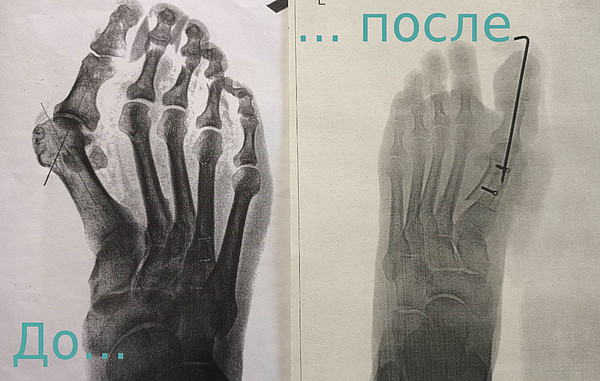

Специалисты дневного стационара Центра травматологии быстро и эффективно лечат вальгусную деформацию и другие заболевания стоп